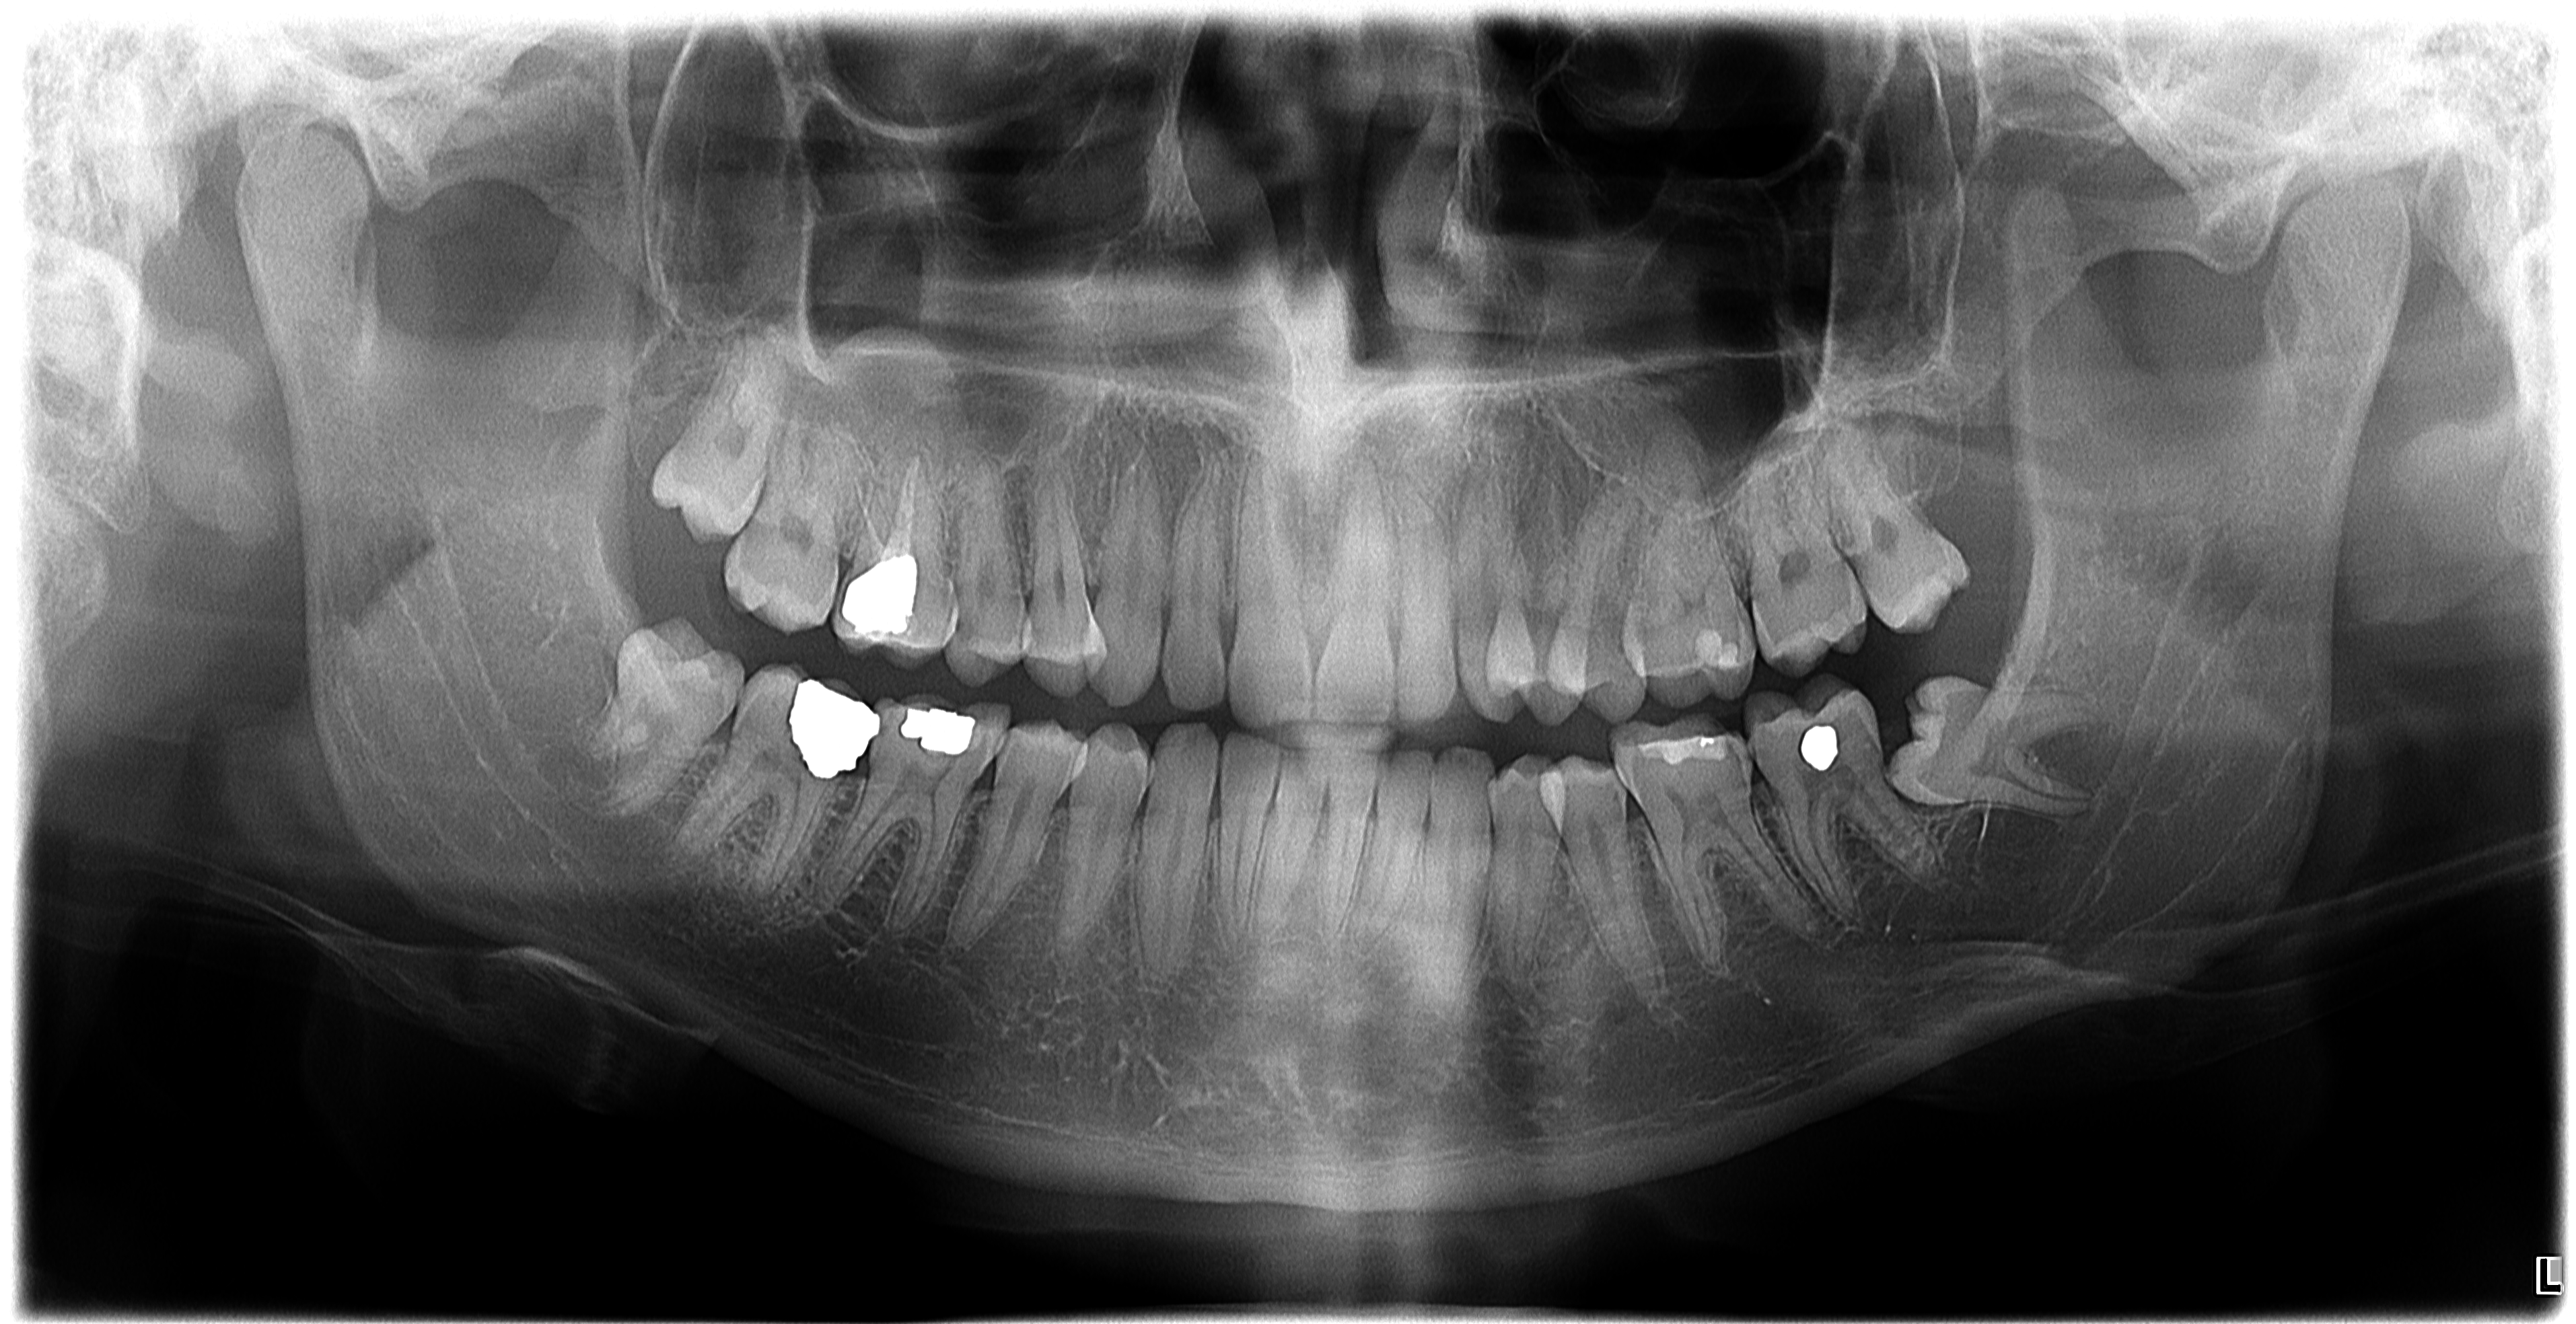

So this is my otropan (scan of my teeth), i have a narrow maxilla, crowding teeth and cant mew for 5 fucking seconds, so my mse deffo wouldnt be for cosmetic reasons, but also i have a slightly higher ipd bc of my right eye (since my right side of maxilla is wider then left) and prominent zygos (they could be more ofc) and because of that i cant make my mind if i should do it. Help.

they are barely crowded